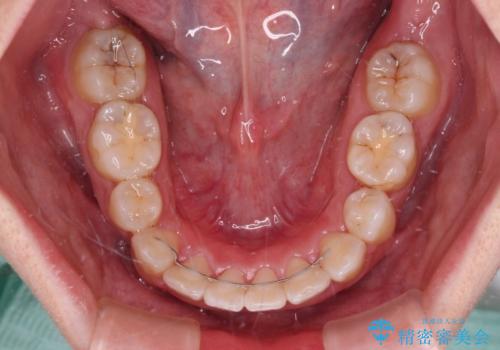

気になっていた八重歯は装置装着から3か月ほどで解消されました。

2年以内を目標として治療を開始しましたが、1年半ほどで終えることができました。